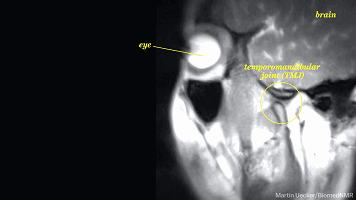

眼睛

这时候由于肾上腺素分泌的原因

你可能会出现短暂的瞳孔放大,眼睛的

焦距增强,当然了你可能不会有太大

明显的视觉上的变化,但有研究证明

人在情绪激动的时候瞳孔可以放大到原来

的5-10倍左右,进入一种精神亢奋的状态

这时候的人眼往往看起来更大更有神,甚至

你会觉得对方眼睛在发光